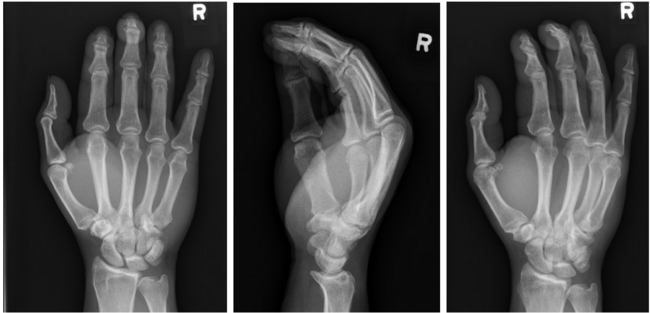

After a delay due to insurance issues, 9 days post-injury the patient underwent operative exploration and repair. Based on the assumption that this was a jersey finger, a Brunner incision was made over the small finger to expose the flexor tendon sheath. Surprisingly, both superficial and deep flexor tendons were intact. The A1 pulley was incised, and retraction of both tendons resulted in appropriate flexion of the finger. There was laxity of the FDP tendon proximally, indicating a proximal rupture. The incision was extended to the distal edge of the carpal tunnel where the distal stump was identified (Figure 2). Release of the transverse carpal ligament was performed, which revealed the small finger FDP tendon rupture at the level of the lumbrical origin (Figure 3). There was significant tenosynovitis involving the middle, ring, and small finger flexor tendons.

Figure 2. Distal stump of small finger FDP tendon.

Figure 3. Forceps holds proximal stump of small finger FDP tendon within the carpal tunnel.